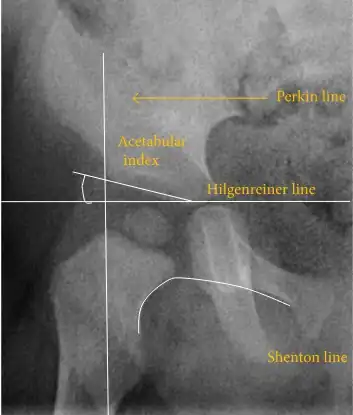

The most useful lines and angles that can be drawn in the pediatric pelvis assessing hip dysplasia are as follows:[50] Different measurements are used in adults.[50]

![Hip dysplasia.[50]](./_assets_/X-ray_of_measurements_in_hip_dysplasia.jpg)